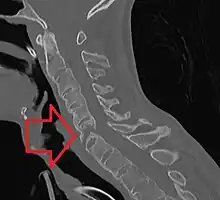

Fracture of the T5 and C7 vertebra due to trauma in a person with ankylosing spondylitis as seen on a CT scan

Prognosis is related to disease severity.[9] AS can range from mild to progressively debilitating and from medically controlled to refractory. Some cases may have times of active inflammation followed by times of remission resulting in minimal disability while others never have times of remission and have acute inflammation and pain, leading to significant disability.[9] As the disease progresses, it can cause the vertebrae and the lumbosacral joint to ossify, resulting in the fusion of the spine.[35] This places the spine in a vulnerable state because it becomes one bone, which causes it to lose its range of motion as well as putting it at risk for spinal fractures. This not only limits mobility but reduces the affected person's quality of life. Complete fusion of the spine can lead to a reduced range of motion and increased pain, as well as total joint destruction which could lead to a joint replacement.[36]

Osteoporosis is common in ankylosing spondylitis, both from chronic systemic inflammation and decreased mobility resulting from AS. Over a long-term period, osteopenia or osteoporosis of the AP spine may occur, causing eventual compression fractures and a back "hump".[37] Hyperkyphosis from ankylosing spondylitis can also lead to impairment in mobility and balance, as well as impaired peripheral vision, which increases the risk of falls which can cause fracture of already-fragile vertebrae.[37] Typical signs of progressed AS are the visible formation of syndesmophytes on X-rays and abnormal bone outgrowths similar to osteophytes affecting the spine. In compression fractures of the vertebrae, paresthesia is a complication due to the inflammation of the tissue surrounding nerves.